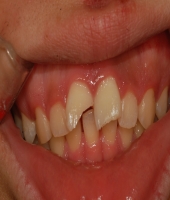

| ● 진료과목 : [심미보철] 돌출치아의 치료

| ● 내용 : 사고로 인한 돌출치아의 치료 |